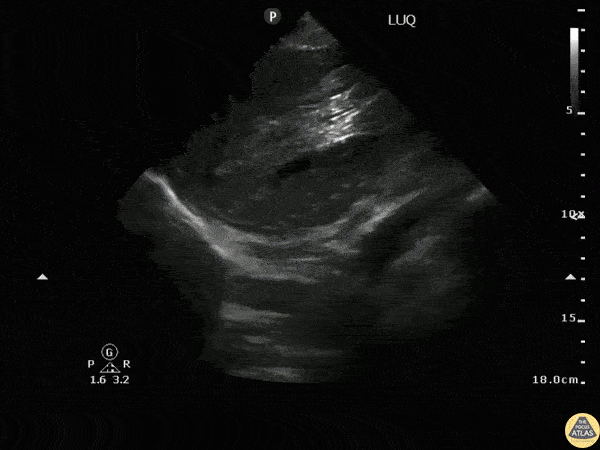

Positive eFAST exam in a blunt trauma patient reveals abnormal splenic architecture and perisplenic fluid. Image courtesy of Robert Jones DO, FACEP @RJonesSonoEM Director, Emergency Ultrasound; MetroHealth Medical Center; Professor, Case Western Reserve Medical School, Cleveland, OH View his original post here